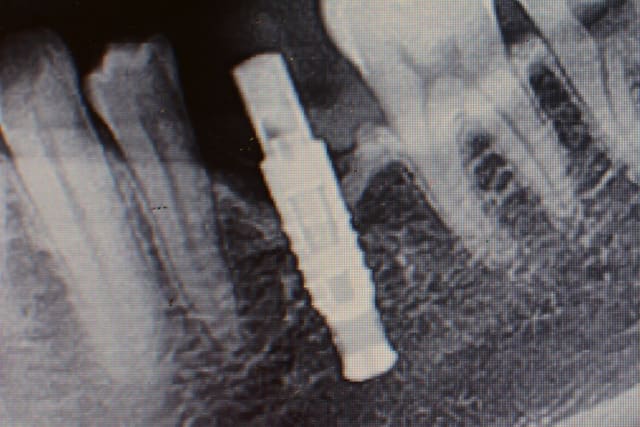

BIS Biotech en 3.6mm de diamètre....hex externe...